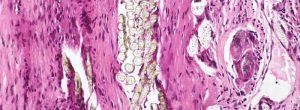

Piedras en las amígdalas: qué son y qué hacer con respecto a ellos